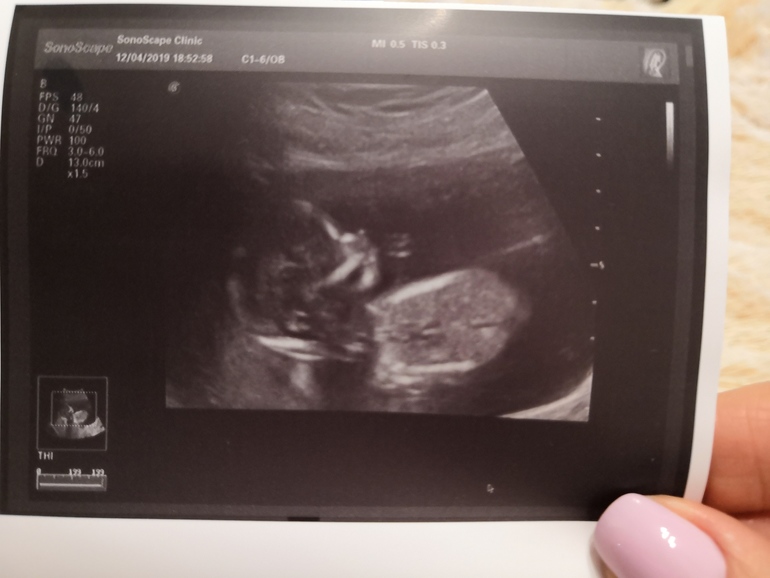

УЗИ, КТГ, доплерБудет у нас девочка! Хотела, чтоб врач сразу не говорила, чтоб сделать вечеринку сюрприз. Но она меня не поняла и сказала пол. Но мы все равно рады. Сейчас нам 16 недель ровно. Развитие по сроку. Посчитала все пальчики. Показала нам все органы.

Посмотрела плаценту. Поднялась на несколько сантиметров!!!!

Длина шейки тоже достаточная. Никакого тонуса. Всё супер)))

Вот она, красотка

А вот тут и ручки видно)))